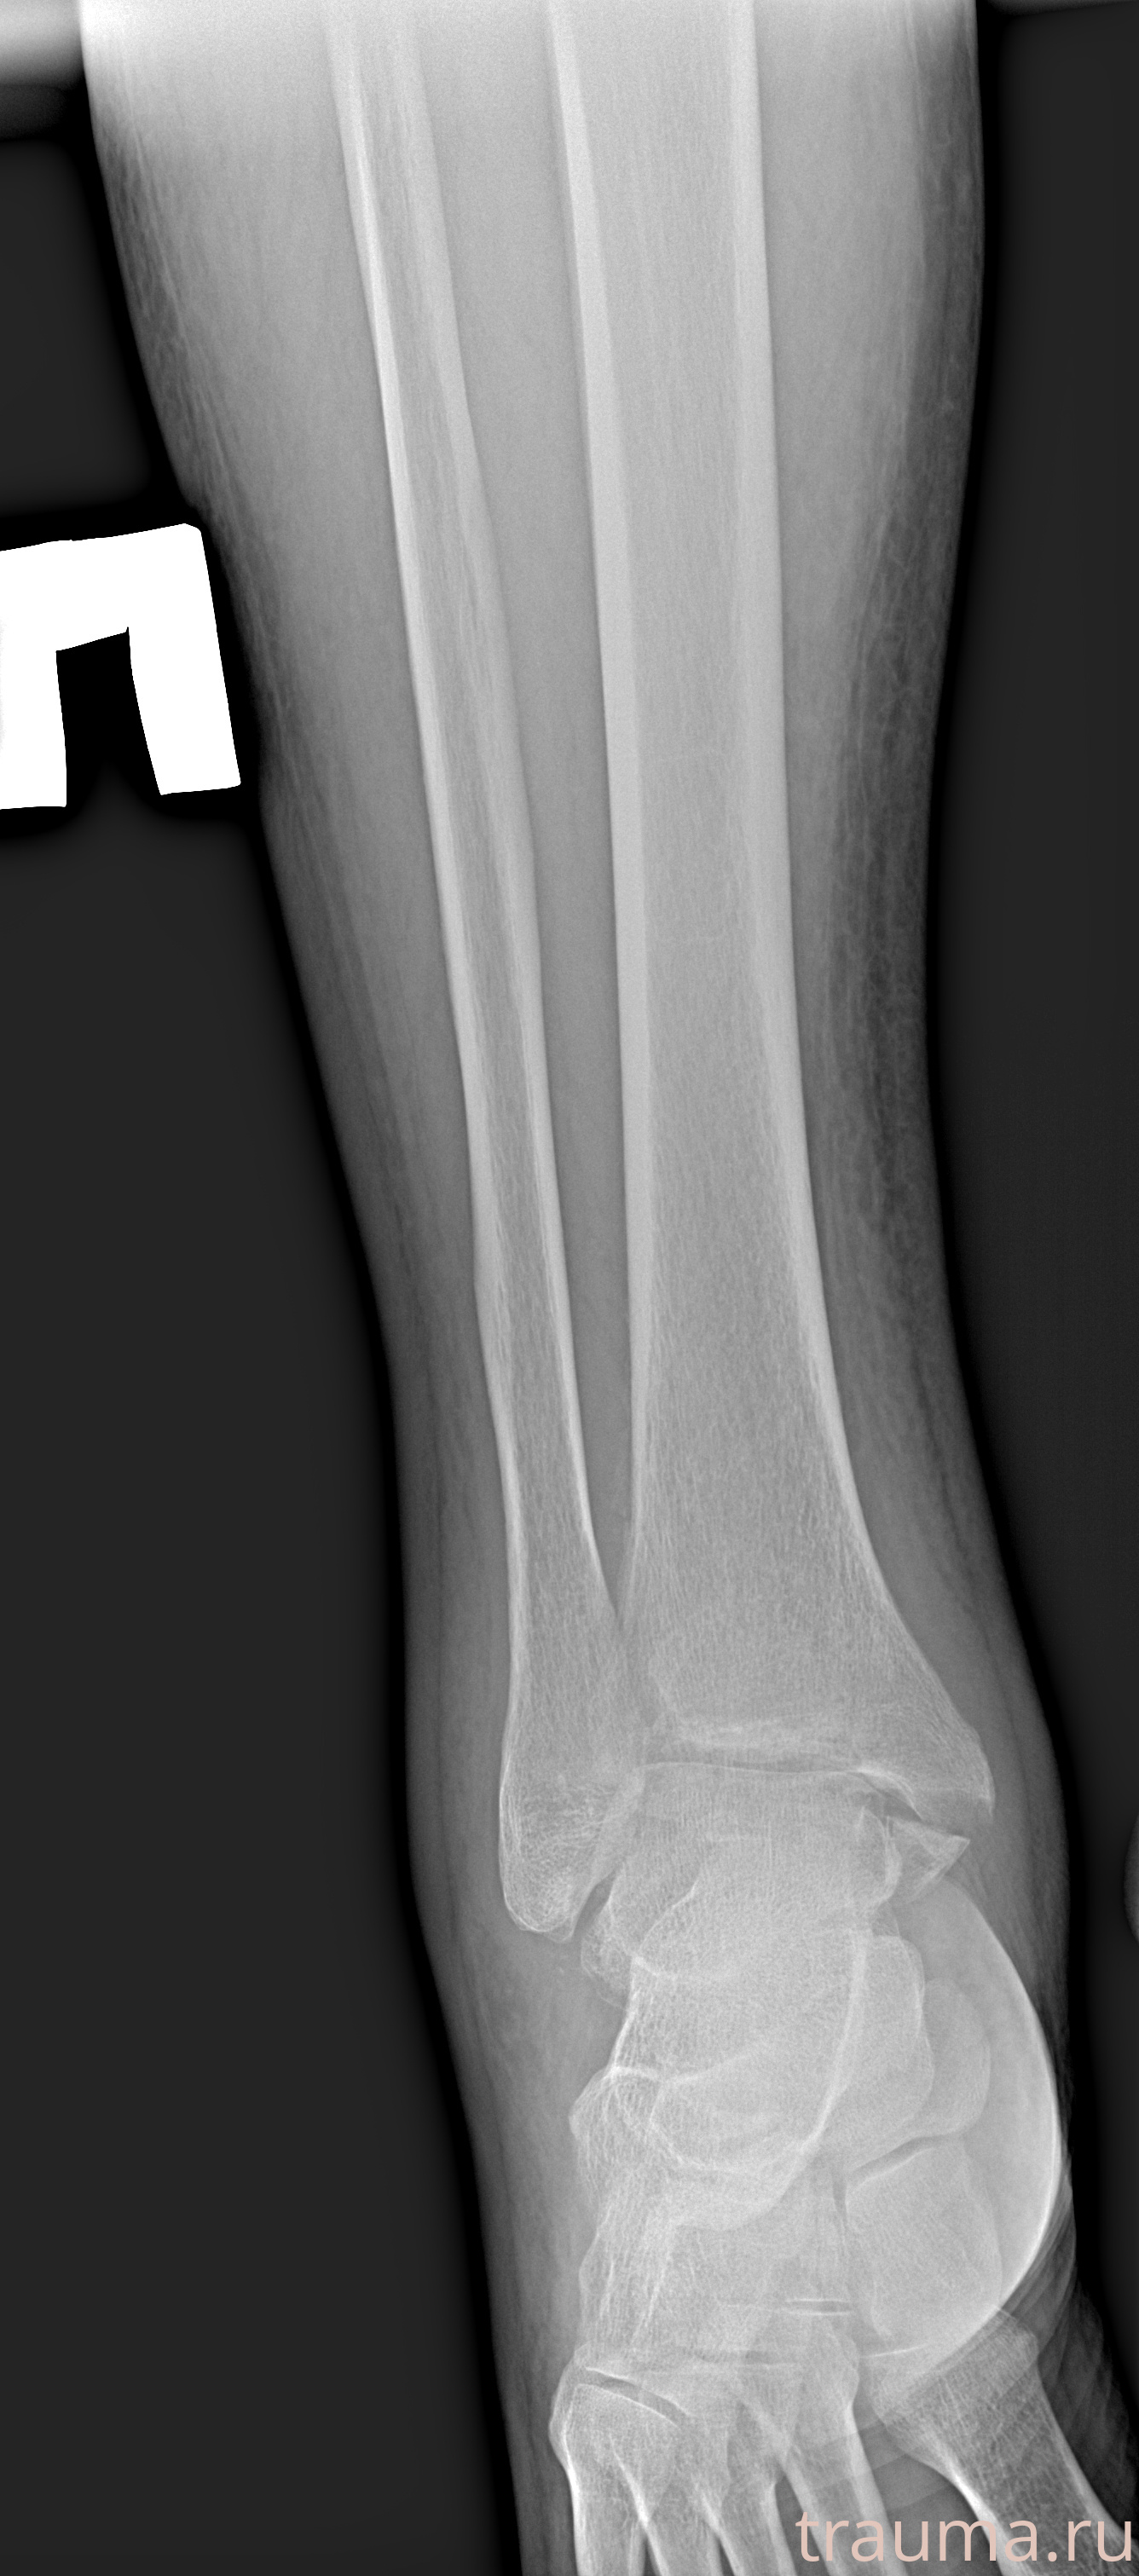

Рентгенограммы